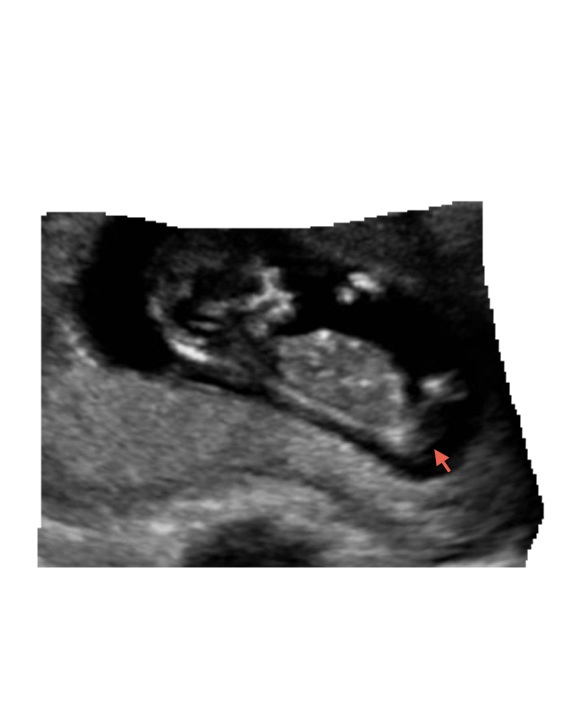

here is one other shot? anyone see anything?Attachment 6634

Maybe boy? It's really dark and hard to tell if that is the nub.